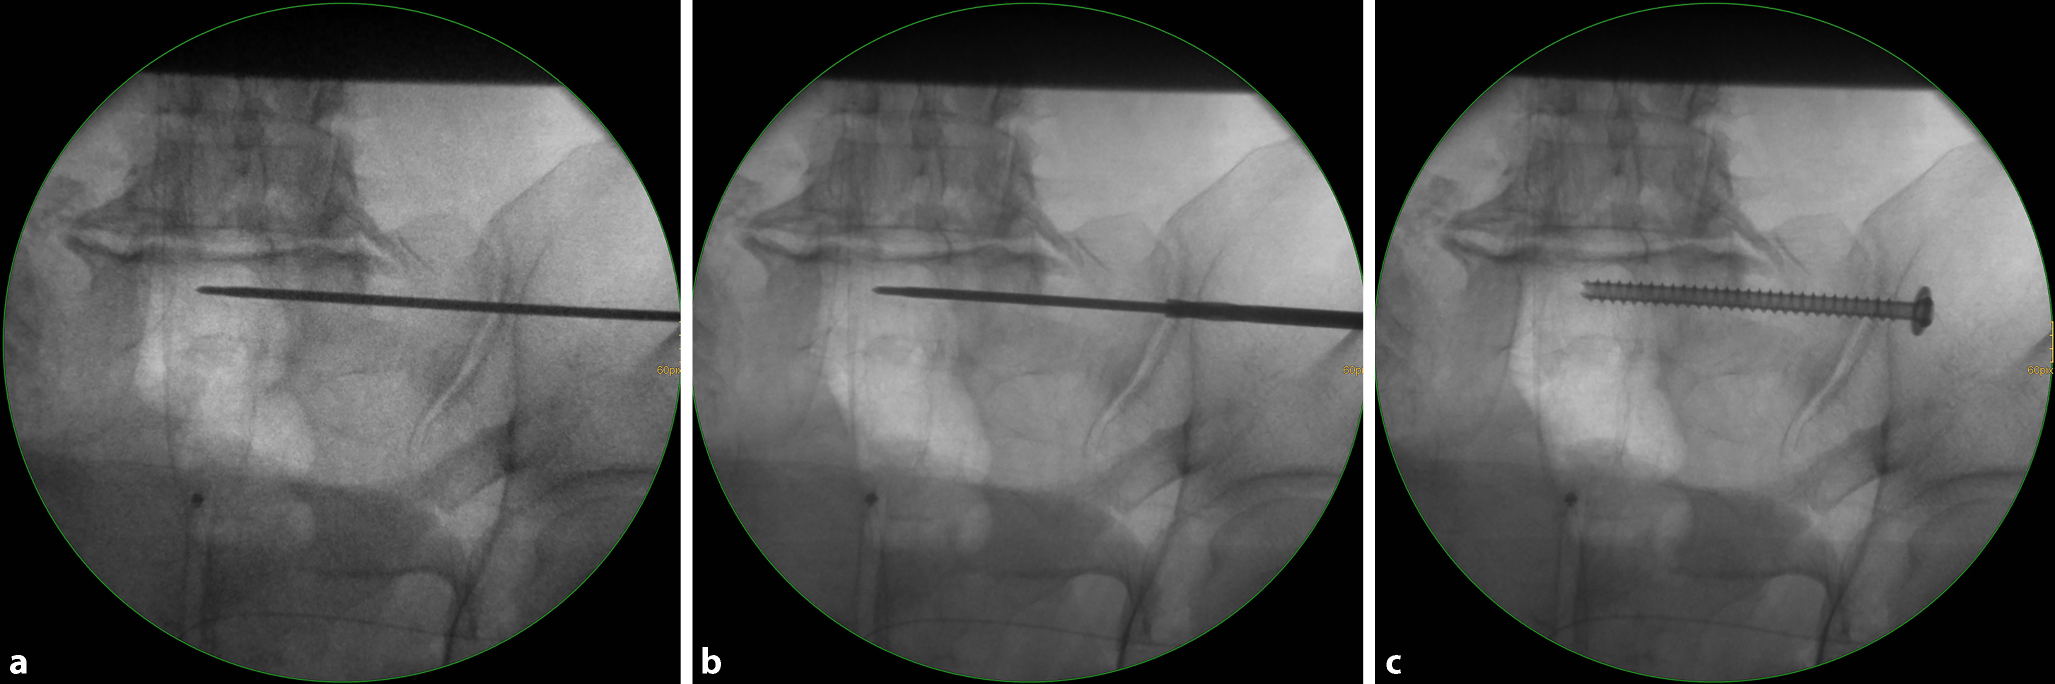

Fig. 7

Advancing the guide wire, predrilling and screw implantation. a The guide wire is advanced across the sagittal midline in transforaminal sacral fractures. In SI joint disruptions the guidewire should be advanced at least to the extent that the thread (16 or 32 mm) is completely medial of the SI joint in order to obtain a lag screw effect. b Predrilling is performed across the SI joint for a total of three cortices. c A cannulated 6.5 mm fully threaded cancellous screw is inserted over the guide wire as a position screw without compression of the transforaminal sacral fracture